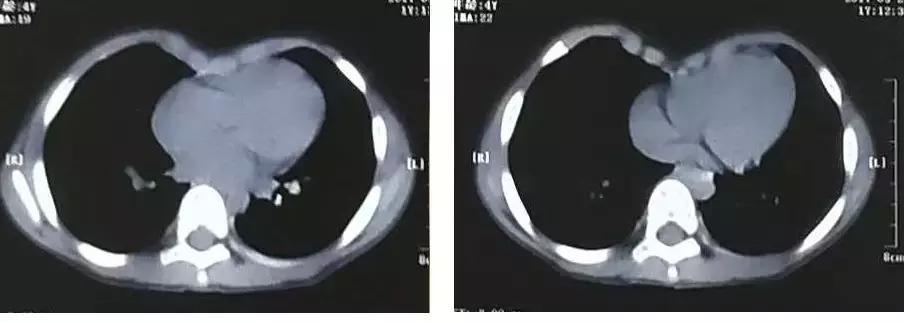

术 前 术 后

副主任医师张涛接诊了患儿,住院后,对小展进行胸壁三维重建等检查

在全麻的状态下,进行了改良微创NUSS手术

手术时间只用了40分钟,只在患儿右侧胸壁腋中线前切开一个约3cm大小切口,术后胸腔无需留置引流管。

手术后第5天,孩子就出院啦。